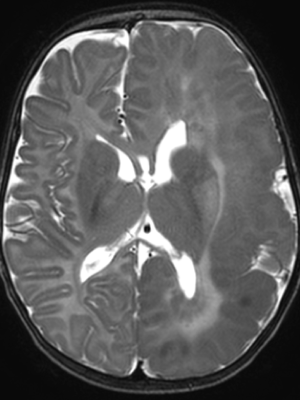

An MRI revealed that Maryam had hemimegalencephaly, a rare neurological condition where one half of the brain is enlarged and can cause epilepsy, developmental delays and muscle weakness. In this case, it had affected the left hemisphere of Maryam’s brain. She was immediately rushed to The Hospital for Sick Children (SickKids).

And at every step, the Interventional Neuroradiology team, Epilepsy and Neurosurgery teams worked together, using detailed electroencephalogram (EEG) and brain MRI scans to ensure precision and safety.